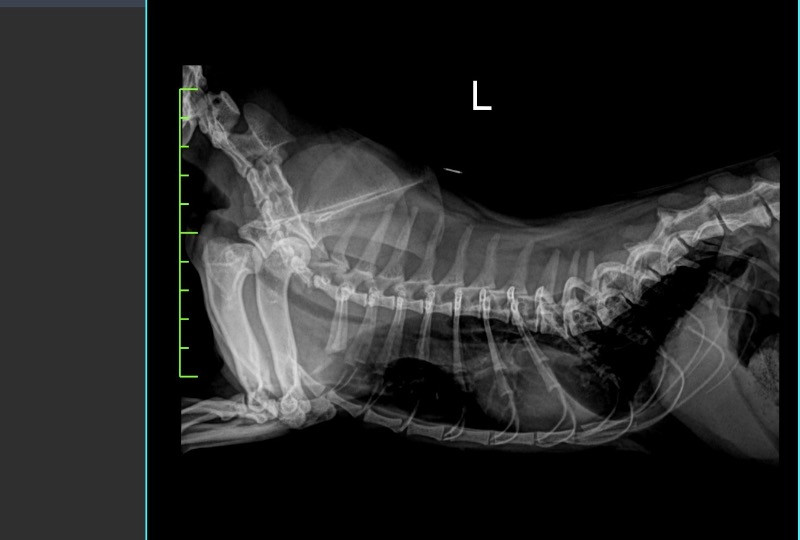

Anni安妮???????? 2026-02-13 貓咪10月大想詢問還有沒有機會不要透過開刀之外的方式矯正背部脊椎凹陷的問題 目前是透過骨科專科穿矯正馬甲將下腹骨骼拉開讓胸腔部分擴大 減少肺及心臟壓迫 0 分享–– 我也要提問